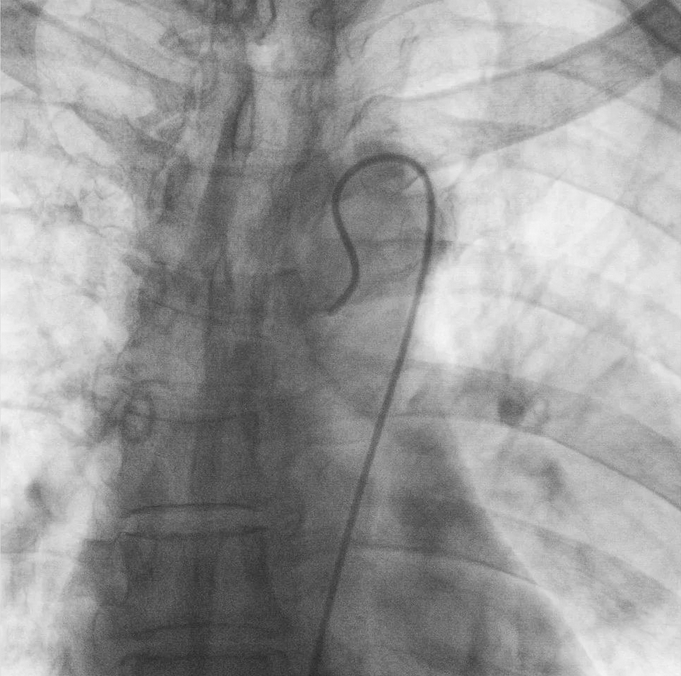

支氣管動脈栓塞+化療灌注術

在普愛醫療移動式平板介入中C影像的引導下,醫生為患者實施雙側支氣管動脈栓塞+化療灌注術。

在微導絲的配合下,先后分別超選擇①至3支左側支氣管動脈腫瘤供血動脈,經微導管推注栓塞微粒球栓塞腫瘤動脈。栓塞結束后,再次用移動式平板介入中C做造影檢查,見腫瘤染色消失。